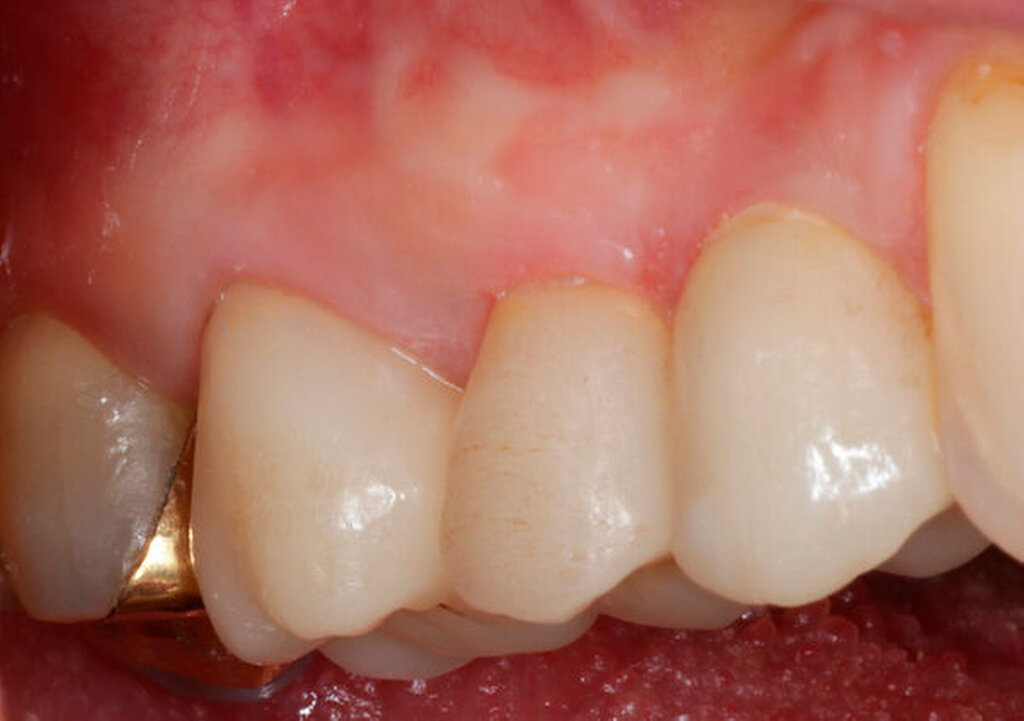

Im Rahmen der Versorgung erfolgte auch ein Austausch der Extensionsbrücke 16–14 durch Einzelkronen auf 16 und 15 sowie einer Implantatversorgung mit Einzelkrone in Regio 014. Der Erhalt des Zahnes 16 ermöglichte so eine wenig invasive Versorgung des ersten Quadranten mit guter Hygienefähigkeit. Alternativ wäre bei Extraktion des Zahnes die Versorgung beispielsweise mit einer ausgedehnten Brückenkonstruktion von 13–17 oder einem weiteren Implantat in Regio 016, vermutlich mit (indirektem) Sinuslift, notwendig gewesen. So konnte der Fall minimalinvasiv zufriedenstellend gelöst werden. Die Patientin ist seit dem Eingriff beschwerdefrei und kommt gut zurecht. Die Situation ist nun seit sechs Jahren stabil.

Darauf erfolgte die Amputation der palatinalen Wurzel mit anschließender Versorgung durch eine vollkeramische Krone. Die Situation ist nach inzwischen drei Jahren weiterhin stabil, die Patientin kommt mit der Versorgung gut zurecht, lediglich palatinal finden sich leicht erhöhte Sondierungstiefen.